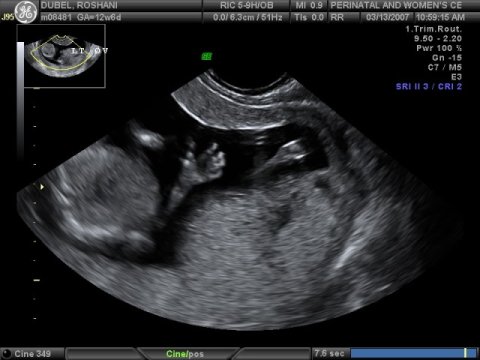

March 14, 2007

The

due date for Baby Miracle keeps changing. Original due date was

September 06, 2007, but an early ultrasound suggested September 19,

2007. Latest ultrasound, done on March 13, 2007, suggest that the

baby is expected to arrive September 09, 2007. It's still too

early to tell the sex of the baby but we should know by late

April/early May.

Baby waves "hello"